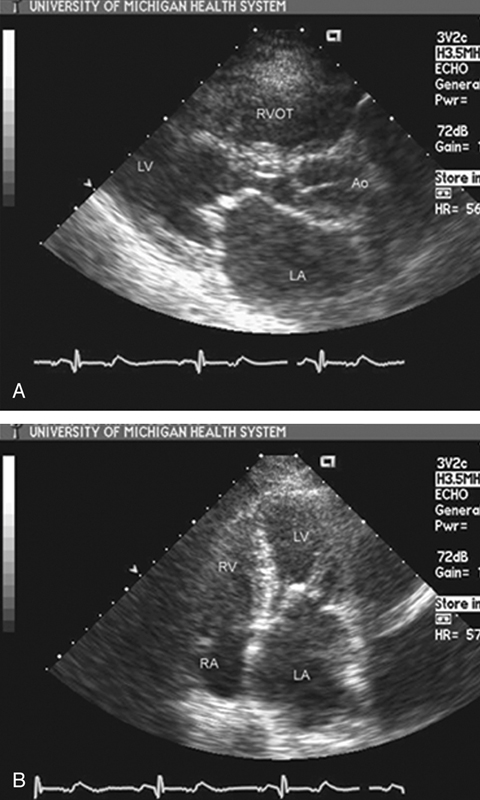

فحوصات تشخيصية لبعض امراض القلب والشرايين التاجية